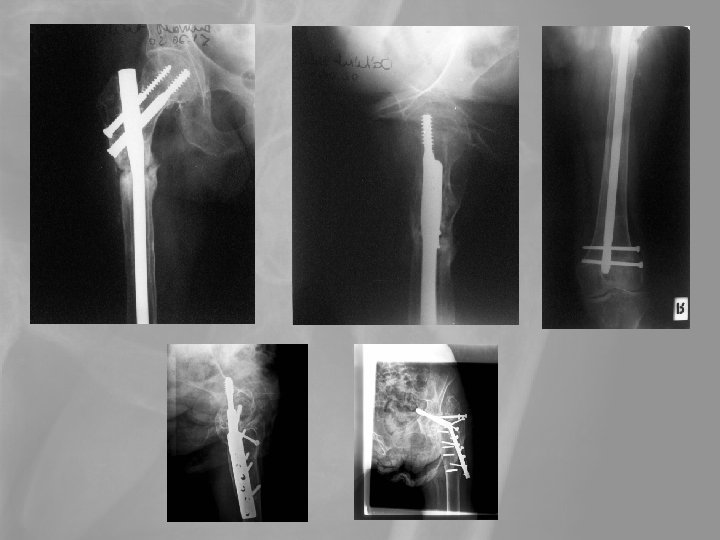

Delayed revision 73 y female. Failed primary stabilisation, Delayed septic complication Pyarthros coxae, septic diaphyseal nonunion. Exarticulation?

Delayed revision Op. sec. Girdlestone+open plate-osy. Secondary wound granulation

Keresztek… T. M. 60 é. Nő -6 év: Fr. cruris l. s. Műtétek: Felfúráros velőűrszegezés UTN ENDER-szegezés, fibula-OT ASP DC-lemezelés ASP Mankóval jár 2006 05 10 fémkivétel, decorticatio, ASP Sebgyógyulás után járógipsz 2006 07 07 Kontroll: gipszeltáv. 2006 07 17 fedett FRVSZ 2006. 09. 08 Kontroll: 1 bottal jár a biztonságért. Térdflexio 0 -120, bokamozgás 0 -0 -30. Terhelve járhat, kontroll decemberben, pénteki napon

67é nő, szártörés, -2év, 3 revisio, fertőzés 85é nő, önellátó, 2 bottal jár Keresztek…